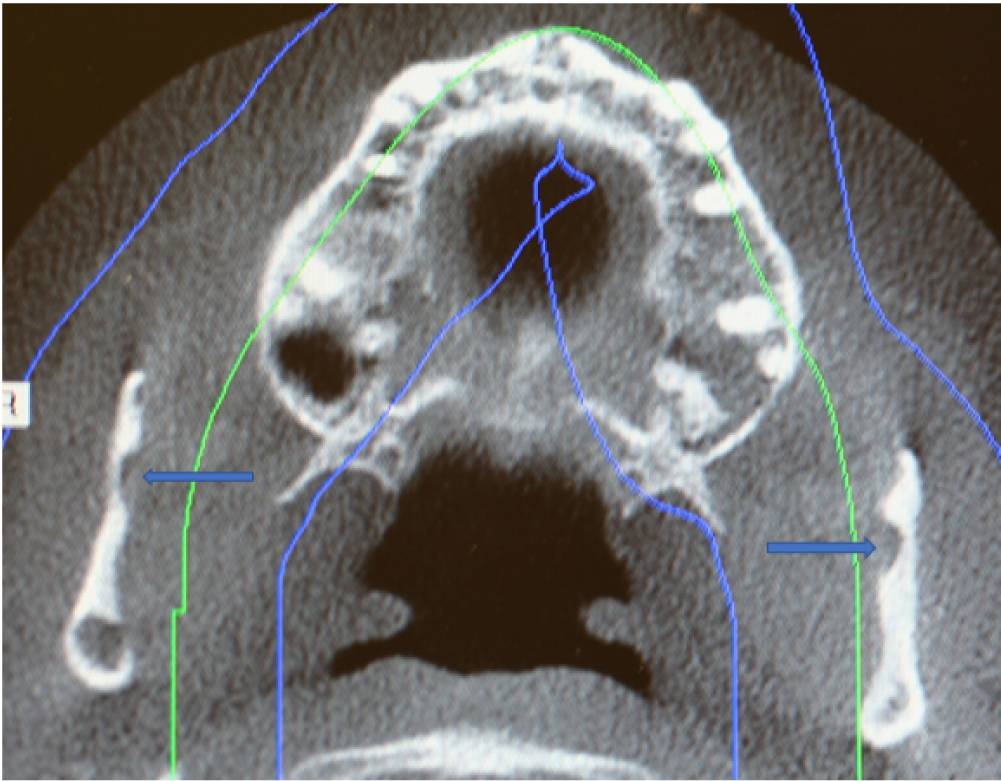

Figure 3: Axial cone beam CT scan showing SBC (Blue arrows) with herniation of soft tissue of the bilateral ramus of the mandible. View Figure 3

There is a paucity of published case reports of SBC in the subcondylar or ascending ramus of the mandible in the English world medical and dental literature [9-19]. Ertas, et al. [14] described two SBC localized to the right ramus in their case report. An atypical variant in the subcondylar region of the mandible near the parotid gland was first reported by Wolf [9] and later Barker [10]. Both authors described the variant as a "parotid or ramus" variant of the Stafne bone cavity. In 2004, Campos, et al. [11] using cone beam CT scan technology reported a parotid gland variant of the SBC as a salivary gland defect. Using computed tomography Sisman, et al. [3] showed that the SBC is due to the presence of aberrant submandibular gland tissue entrapped within the osseous defect on the medial surface of the mandible. Based on these findings, the authors of this report hypothesize that in our patient parenchymal tissue of the bilateral parotid gland became entrapped in the developing ramus of the mandible that could lead to a similar osseous concavity (Figure 3) [20]. Based on the number of cases reported, SBC localized to the unilateral ramus is considered a rare variant. To the best of our knowledge, there are less than twelve case reports of SBC localized to this area of the mandible. In our reported case, bilateral ramus involvement is even rarer.